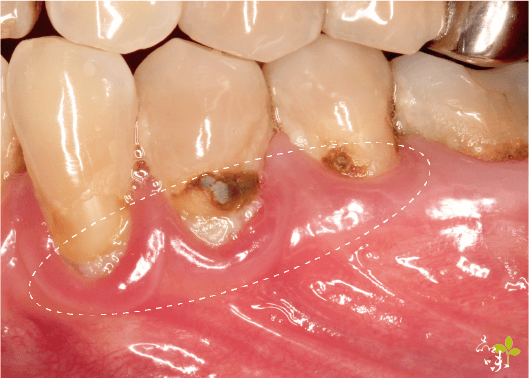

牙齦萎縮的過程很慢,不太容易被察覺,很多患者都是覺得最近吃東西、喝飲料感到痠痛敏感來就診,醫生檢查後,可能發現有這幾種狀況:

- 某幾顆牙齒齒頸部露出、形成一個 V 字型。

- 假牙邊緣外露,牙冠以下露出來。

牙周病會造成齒槽骨破壞,進而導致牙齦隨齒槽骨消失而後退,這時建議先進行牙周病治療才是上策。

而當牙齒已經出現鬆動或嚴重動搖的情形時,甚至是需要拔牙的情況,針孔微創牙齦手術是無效的。